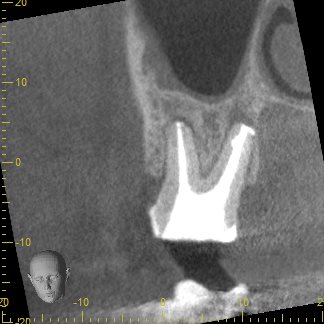

3ヶ月経過後のCT画像です。

術前のCT画像と比較すると、歯根周囲の黒くなっていた部分の骨の回復を認めました😊

ここまで回復すれば長期的な安定期が期待できるため、被せ物を作製していきます。